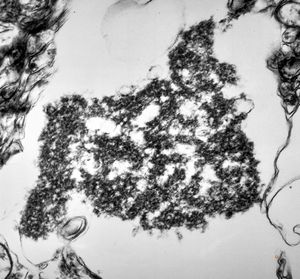

F,50y. | progressive multifocal leukoencephalopathy- viral particles in a glial cell

F,50y. | progressive multifocal leukoencephalopathy- viral particles in a glial cell

F,50y. | progressive multifocal leukoencephalopathy- viral particles in a glial cell